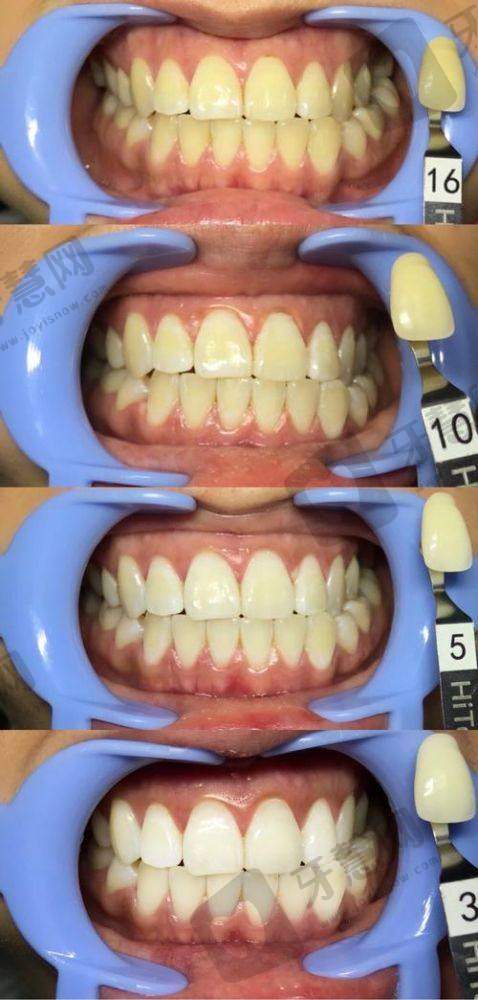

科室设置与诊疗项目:科室设置涵盖口腔多个领域,提供烤瓷牙、全瓷牙、牙齿美白、口内治疗、牙齿修复、儿童齿科、牙齿矫正、牙齿种植等多种诊疗项目。

厦门百姓口腔医院在业内拥有良好的口碑和较高的认可度。从患者反馈来看,许多患者对医院的服务和治疗成效给予高度评价。有患者表示,面诊多家牙科后,百姓口腔推荐的牙齿贴片便宜又好,解决了大小牙、牙齿不白等问题,感觉特别良心。还有患者在接受前牙根管治疗后,称赞医院环境干净整洁,医生十分正规,耐心解释每一个治疗步骤,术后回访也特别贴心。在行业内,医院凭借精良的设备、专精的医生团队和优质的服务,在当地人分享的厦门牙科医院实力排名中占据一定位置,其牙齿矫正、牙齿修复等项目更是得到广泛认可。

评价一:我一直对自己的牙齿不太满意,有大小牙和牙齿不白的问题。之前面诊了好多牙科,都建议我做牙齿矫正。来到百姓口腔后,医生推荐了牙齿贴片,价格实惠成效还好。贴上之后,牙齿变得整齐又洁白,一下就解决了我的困扰。而且医院环境干净整洁,医生和工作人员都特别热情,真的是一家良心医院,强烈推荐!

厦门百姓口腔医院的收费价格合理透明。在2025年厦门德国威兰德牙冠价目表中,其德国威兰德牙冠价格为2536 - 4233元。2023年厦门市隐形活动义齿假牙镶牙修复(单颗)也有明确的收费标准。此外,医院还提供多种口腔服务,如临朐整牙、装扩弓器等。对于不同的诊疗项目,医院会根据患者的具体情况和所选材料进行收费。例如,牙齿矫正的费用会因矫正方式和材料的不同而有所差异;牙齿修复的价格也会根据所使用的烤瓷牙或全瓷牙的种类而变化。总体来说,医院在确保治疗成效和服务质量的前提下,为患者提供了具有性价比的口腔医疗服务。